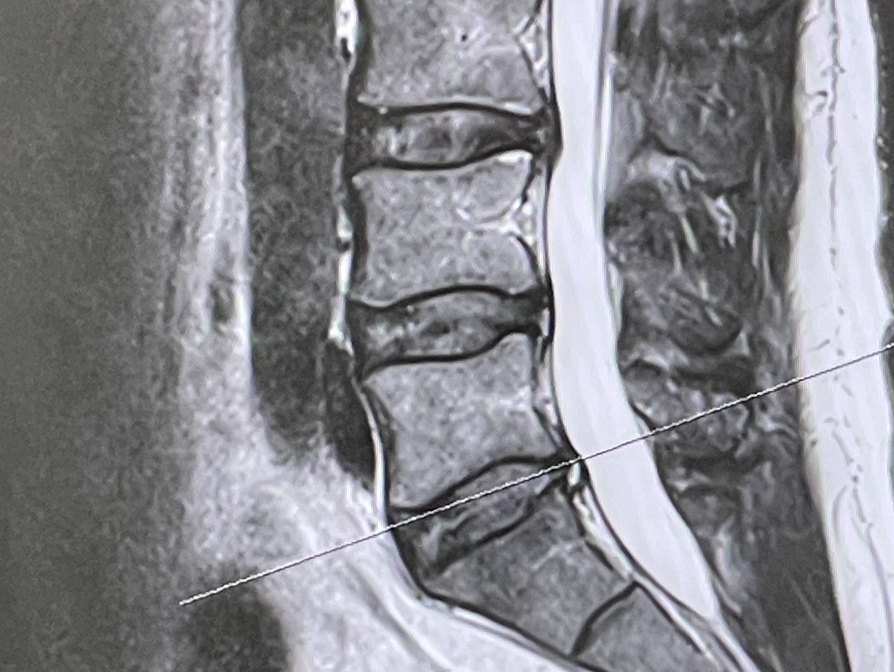

병원 진료를 받았고, MRI를 찍었는데 3번 4번 5번 척추가 다 안 좋았다. 결국 디스크 판정을 받았다. 멈춰야 할 때 멈추지 못했더니 결국에는 사고가 난 것이다. 그나마 초기였고 디스크가 터진 것이 아니라 약간 눌러진 상태에서 탈이 난 것이 긍정적이라면 긍정적인 상황이었다. 재발 방지와 악화되는 것을 예방하기 위해서는 일상생활에서의 바른 자세 유지와 꾸준한 운동을 통한 코어 강화가 중요하다고 했다.